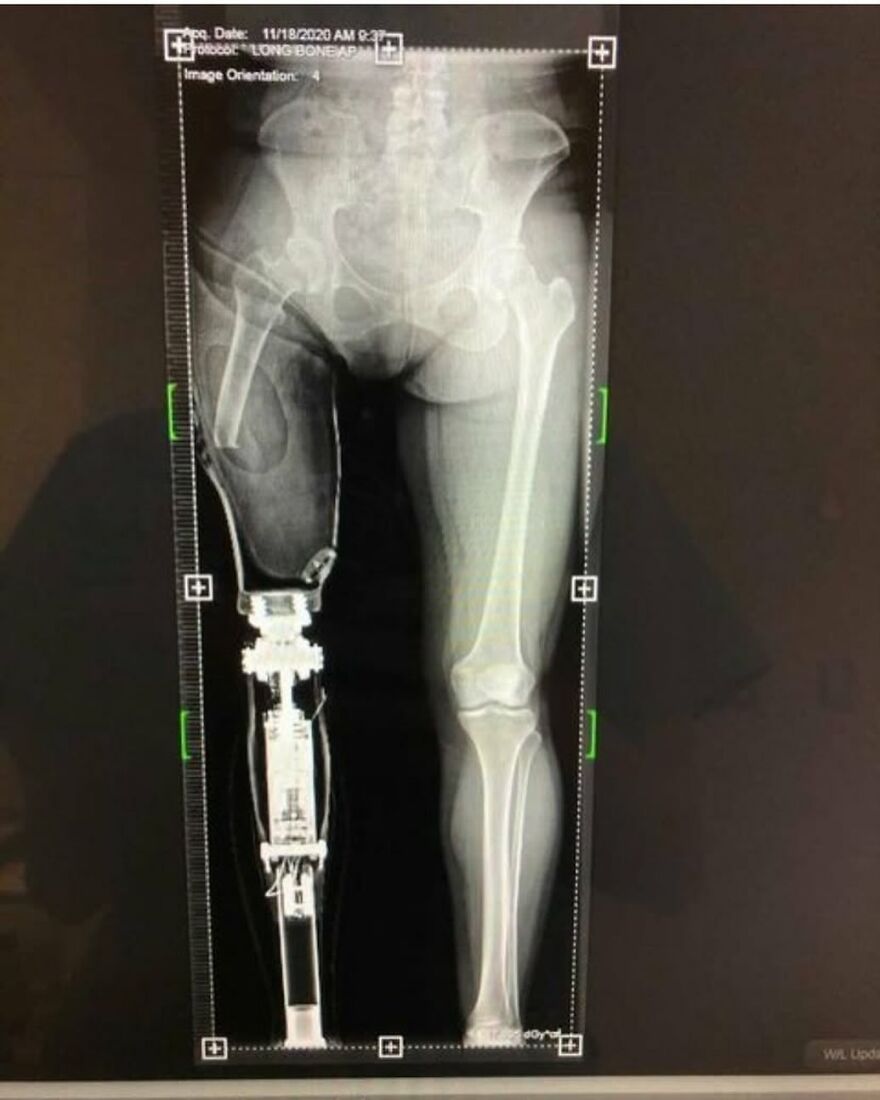

Looks like another" feet on the dashboard" of a car involved in an accident